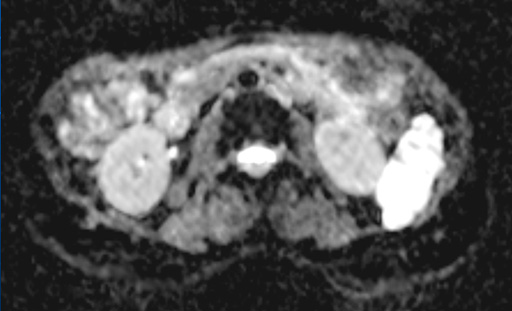

図5 T2強調横断像 図6 拡散強調横断像(b=1000)

図6 拡散強調横断像(b=1000) 図7 ADC画像